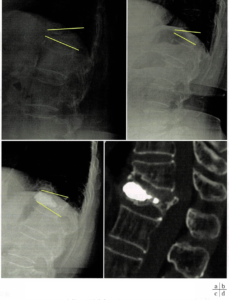

図1 T12椎体骨折に対するBKP術後、隣接椎体骨折の例

a(左上):立位、局所後弯26°

b(右上):仰臥位、局所後弯19°

c(左下):術直後、局所後弯13°

d(右下):術後6か月、CTにて隣接椎体骨折(T11)を認める。

AVFスコアは6点中5点であり、胸腰椎移行部でセメント注入量が多く矯正角度が大きくなれば、隣接椎体骨折が生じやすいということになる。